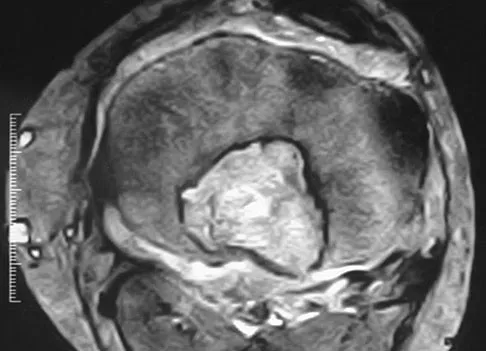

Figures 20a and 20b show the AP and lateral radiographs of a 62-year-old man who has had hip pain for the past 3 weeks. Figure 20c shows a CT scan of the abdomen and pelvis. A needle biopsy specimen is shown in Figure 20d. Preoperative management should include which of the following?

Explanation

The histology shows findings consistent with metastatic renal cell carcinoma. Renal cell carcinoma metastases are extremely vascular. Preoperative embolization helps minimize the amount of blood loss during curettage of these lesions. Chatziioannou AN, Johnson ME, Pneumaticos SG, et al: Preoperative embolization of bone metastases from renal cell carcinoma. Eur Radiol 2000;10:593-596.